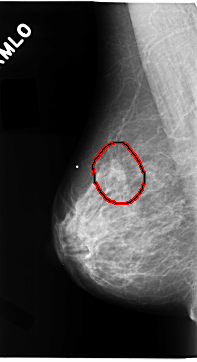

C_0100_1.RIGHT_MLO

RIGHT_MLO LINES 4704 PIXELS_PER_LINE 2560 BITS_PER_PIXEL 12 RESOLUTION 50 OVERLAY

FILE: C_0100_1.RIGHT_MLO.OVERLAY

TOTAL_ABNORMALITIES 1

ABNORMALITY 1

LESION_TYPE MASS SHAPE IRREGULAR MARGINS SPICULATED

ASSESSMENT 5

SUBTLETY 5

PATHOLOGY MALIGNANT

TOTAL_OUTLINES 1

BOUNDARY